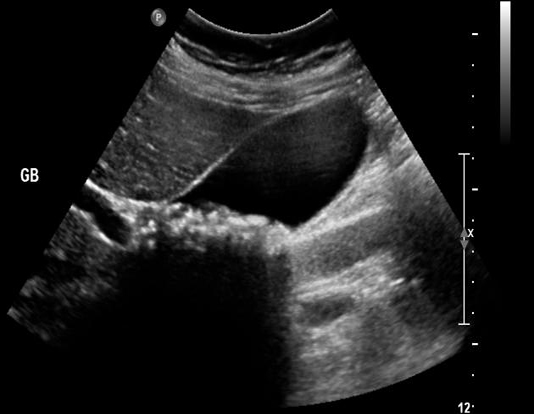

Calcul vesicule biliaire :

Image hyperechogene de 10mm en C forme

avec espace de

vide ascoustique posterieure en voyant tres fine .

Image echographique du foie |

Image echographique

hyperechogene de deux calculs de la vesicule

biliaire . Cone de l'ombre sont en vue tres net |

|

Image de hypoascoustique posterieure de

calcul est toujour en se presentee . Meme cas

en un autre plan de coupe |